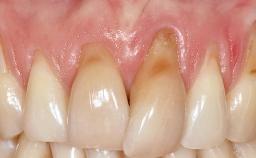

A 30-year-old woman was referred by her general dentist for evaluation of an esthetic complication related to previous implant treatment for congenitally missing maxillary lateral incisors. The patient’s chief complaint was the inadequate esthetic appearance of her smile. The case demonstrates the use of a combined approach to achieve optimal results. Two different flap designs - a tunnel technique and a coronally advanced flap - are employed based on the surgical objectives for the affected site.

Periodontal Phenotype Low-scalloped, thick Medium-scalloped, medium-thick High-scalloped, thin

Soft Tissue Anatomy Intact Defective